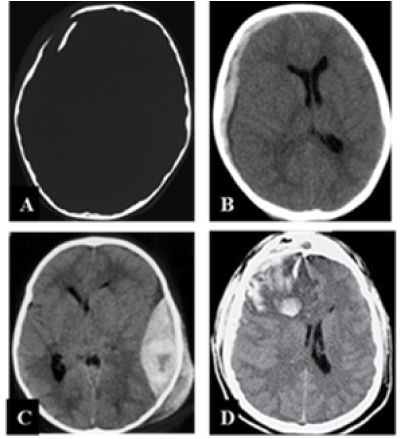

At cerebral CT-scan, extra-dural hematoma (Image1-C) was the most seen followed by depressed skull fractures (Image1-A), onset acute subdural hematoma (Image 1-B) and finally intracranial hypertension caused by cerebral oedema (Image1-D) with respectively 21.6%, 16.3%, 13.5% and 8.1%. 40.5% of children was suffering of associated injuries; they was distributed between maxillofacial injuries (16.2%) and limbs trauma (24.3%). In this latter group it’s noted lower limb fractures (66.7%) and 3 cases of upper limb fractures (33%).

Image 1.Diagnostic brain CT-scan